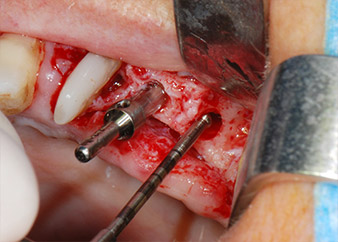

IImplant beds were prepared at sites 25 and 26 with rotary instruments, used in a contra-angle handpiece with a 20 : 1 transmission ratio with an updated powerful implant motor (Implantmed, W&H) (Fig. 8).

The implants (Restore, Keystone Dental, diameter 3,75 mm, length 8.0 mm) were placed with the implant motor (Figs. 11 and 12).